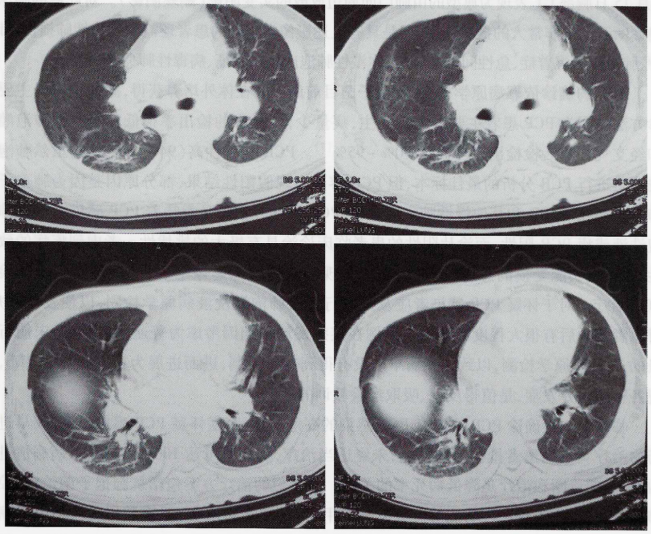

2月15日患者气短症状突然较前加重,咳嗽、胸闷、气短明显,端坐呼吸。调整吸氧方式为储氧面罩吸氧,氧流量10 L/min,复查胸部CT提示以肺门为中心的双侧肺弥漫性磨玻璃及实变影(图2),病灶较2月6日明显加重。复查血气分析(储氧面罩吸氧,氧流量10 L/min):pH 7.518,PaCO2 30.8 mmHg,PaO2 49.3 mmHg,SaO2 86.4%,PaO2/FiO149 mmHg。

图2  2016年2月15日胸部CT:肺门为中心的双侧肺弥漫性磨玻璃及实变影

PJP患者的胸部CT多表现为双肺对称的磨玻璃影、实变影、马赛克征、碎石路征等征象。本病例2月15日胸部CT表现为典型的由肺门向周边放散的实变阴影(蝴蝶阴影),这对此后的临床明确诊断起到了非常大的提示作用,但具有上述影像学表现的患者仍需与药物性肺损伤、肺水肿、肺泡蛋白沉积症、急性间质性肺炎、弥漫性肺泡出血综合征、病毒性肺炎等相鉴别。